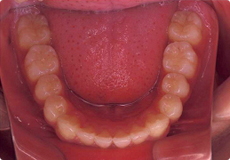

よい歯並びの例

矯正治療では、このような咬み合わせを獲得することが目標の一つとなります。

お口の中には、親知らずを除くと上下で28本の歯がはえます。

隙間や凸凹などもなく、アーチ状にきれいに並んでいます。

上下の真ん中が一致しています。

よい咬み合わせでは、前歯は上の歯が下の歯より2mmくらい前へ出て、同じく2mmくらい重なります。奥歯は、歯の山と谷が歯車のようにしっかり咬み合います。